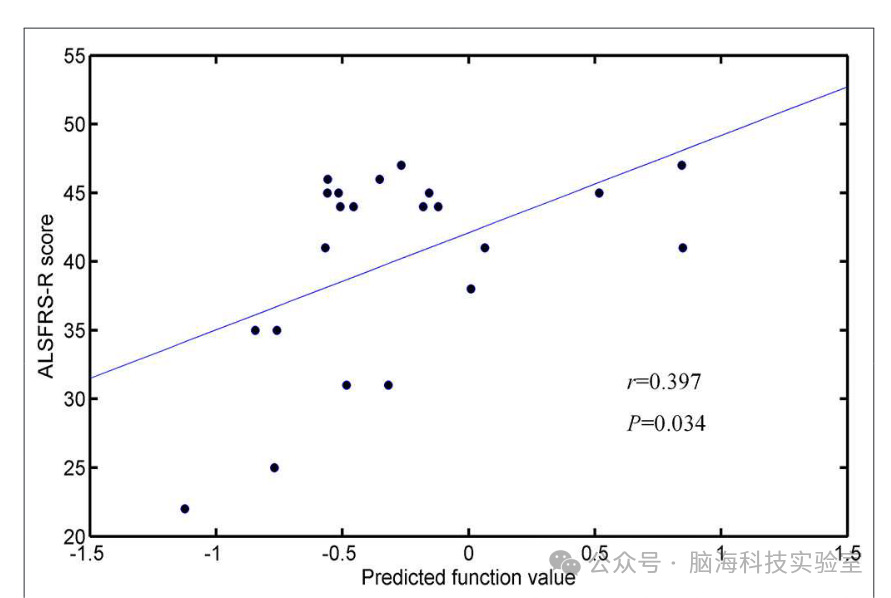

通过以每个受试者的预测函数值作为指标,研究生成了分类器的接收器工作特征(ROC)曲线(图5)。所开发方法的ROC曲线下面积(AUC)为0.862,说明分类的功效相对较强。计算Spearman相关系数以评估预测函数值和ALSFRS-R评分之间的相关性(图6)。研究观察到这些参数之间存在正相关关系(r = 0.0.397,P = 0.034)。

图6

由于肌萎缩侧索硬化症(ALS)的发病率较低(约为5/100,000)以及其异质性本质,对ALS的准确识别和特征描述仍然是一个挑战。研究的研究结果表明,基于机器学习方法,白质的弥散张量成像(DTI)测量可以作为一种替代ALS生物标志物的手段。与之相一致的是,以往的研究也已经展示了扩散测量在群体水平和个体水平识别ALS方面的潜力。受试者工作特征曲线(ROC 曲线)分析以及置换统计检验进一步验证了本研究分类结果的可靠性。此外,研究的结果表明,与其它DTI指标相比,分数各向异性(FA)是识别ALS最有前景的生物标志物,这与以往强调FA变化是ALS一致性的标志的研究结果相一致。此外,研究还观察到支持向量机(SVM)预测函数值与ALS功能评分量表修订版(ALSFRS-R)评分之间的相关性。由于预测函数值是通过将最优特征投影到超平面的权重向量上计算得出的,因此较大的绝对值意味着受试者距离超平面更远,并且对分类的贡献更为显著。因此,研究可以推断,当ALSFRS-R评分更高(即疾病严重程度更高)时,受试者被误分类的可能性更低。

研究发现,当选择2400-3400个特征时,分类准确率最高,达到83.33%(敏感性=77.27%,特异性=88.46%,P=0.0001),ROC曲线下面积(AUC)为0.862。此外,SVM预测函数值与ALSFRS-R评分呈正相关(r=0.397, P=0.034)。